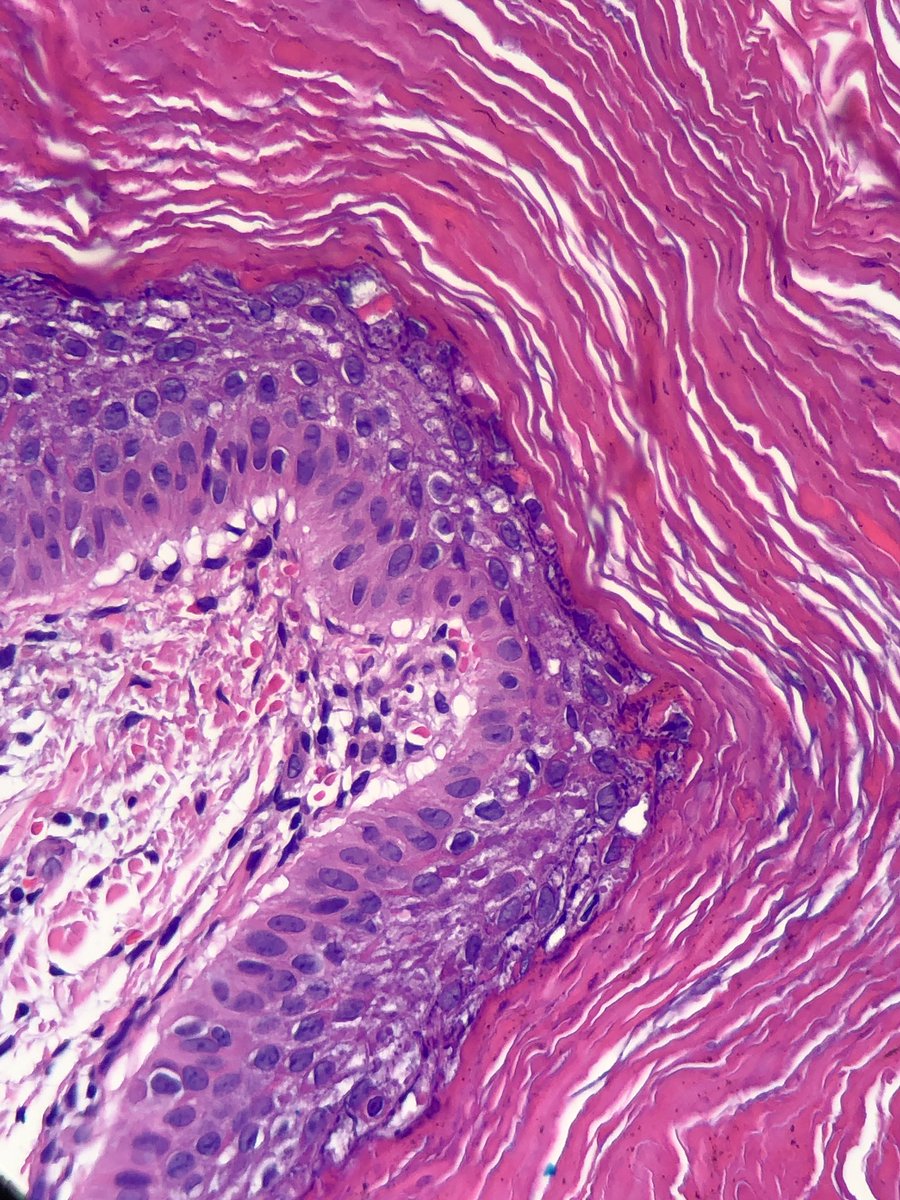

Upper arm. Older patient. @HENRYY_MD you’re only allowed to look at the low power image. Others can look at the high power. @et565 @forthejon @ZachHopkinsMD @DrGeeONE #anyoneelsecananswer #pathology

English